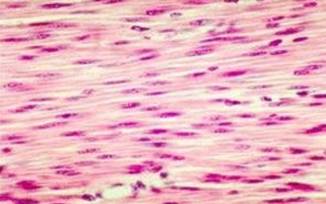

组织分为四种:

上皮组织、结缔组织、

肌肉组织、神经组织